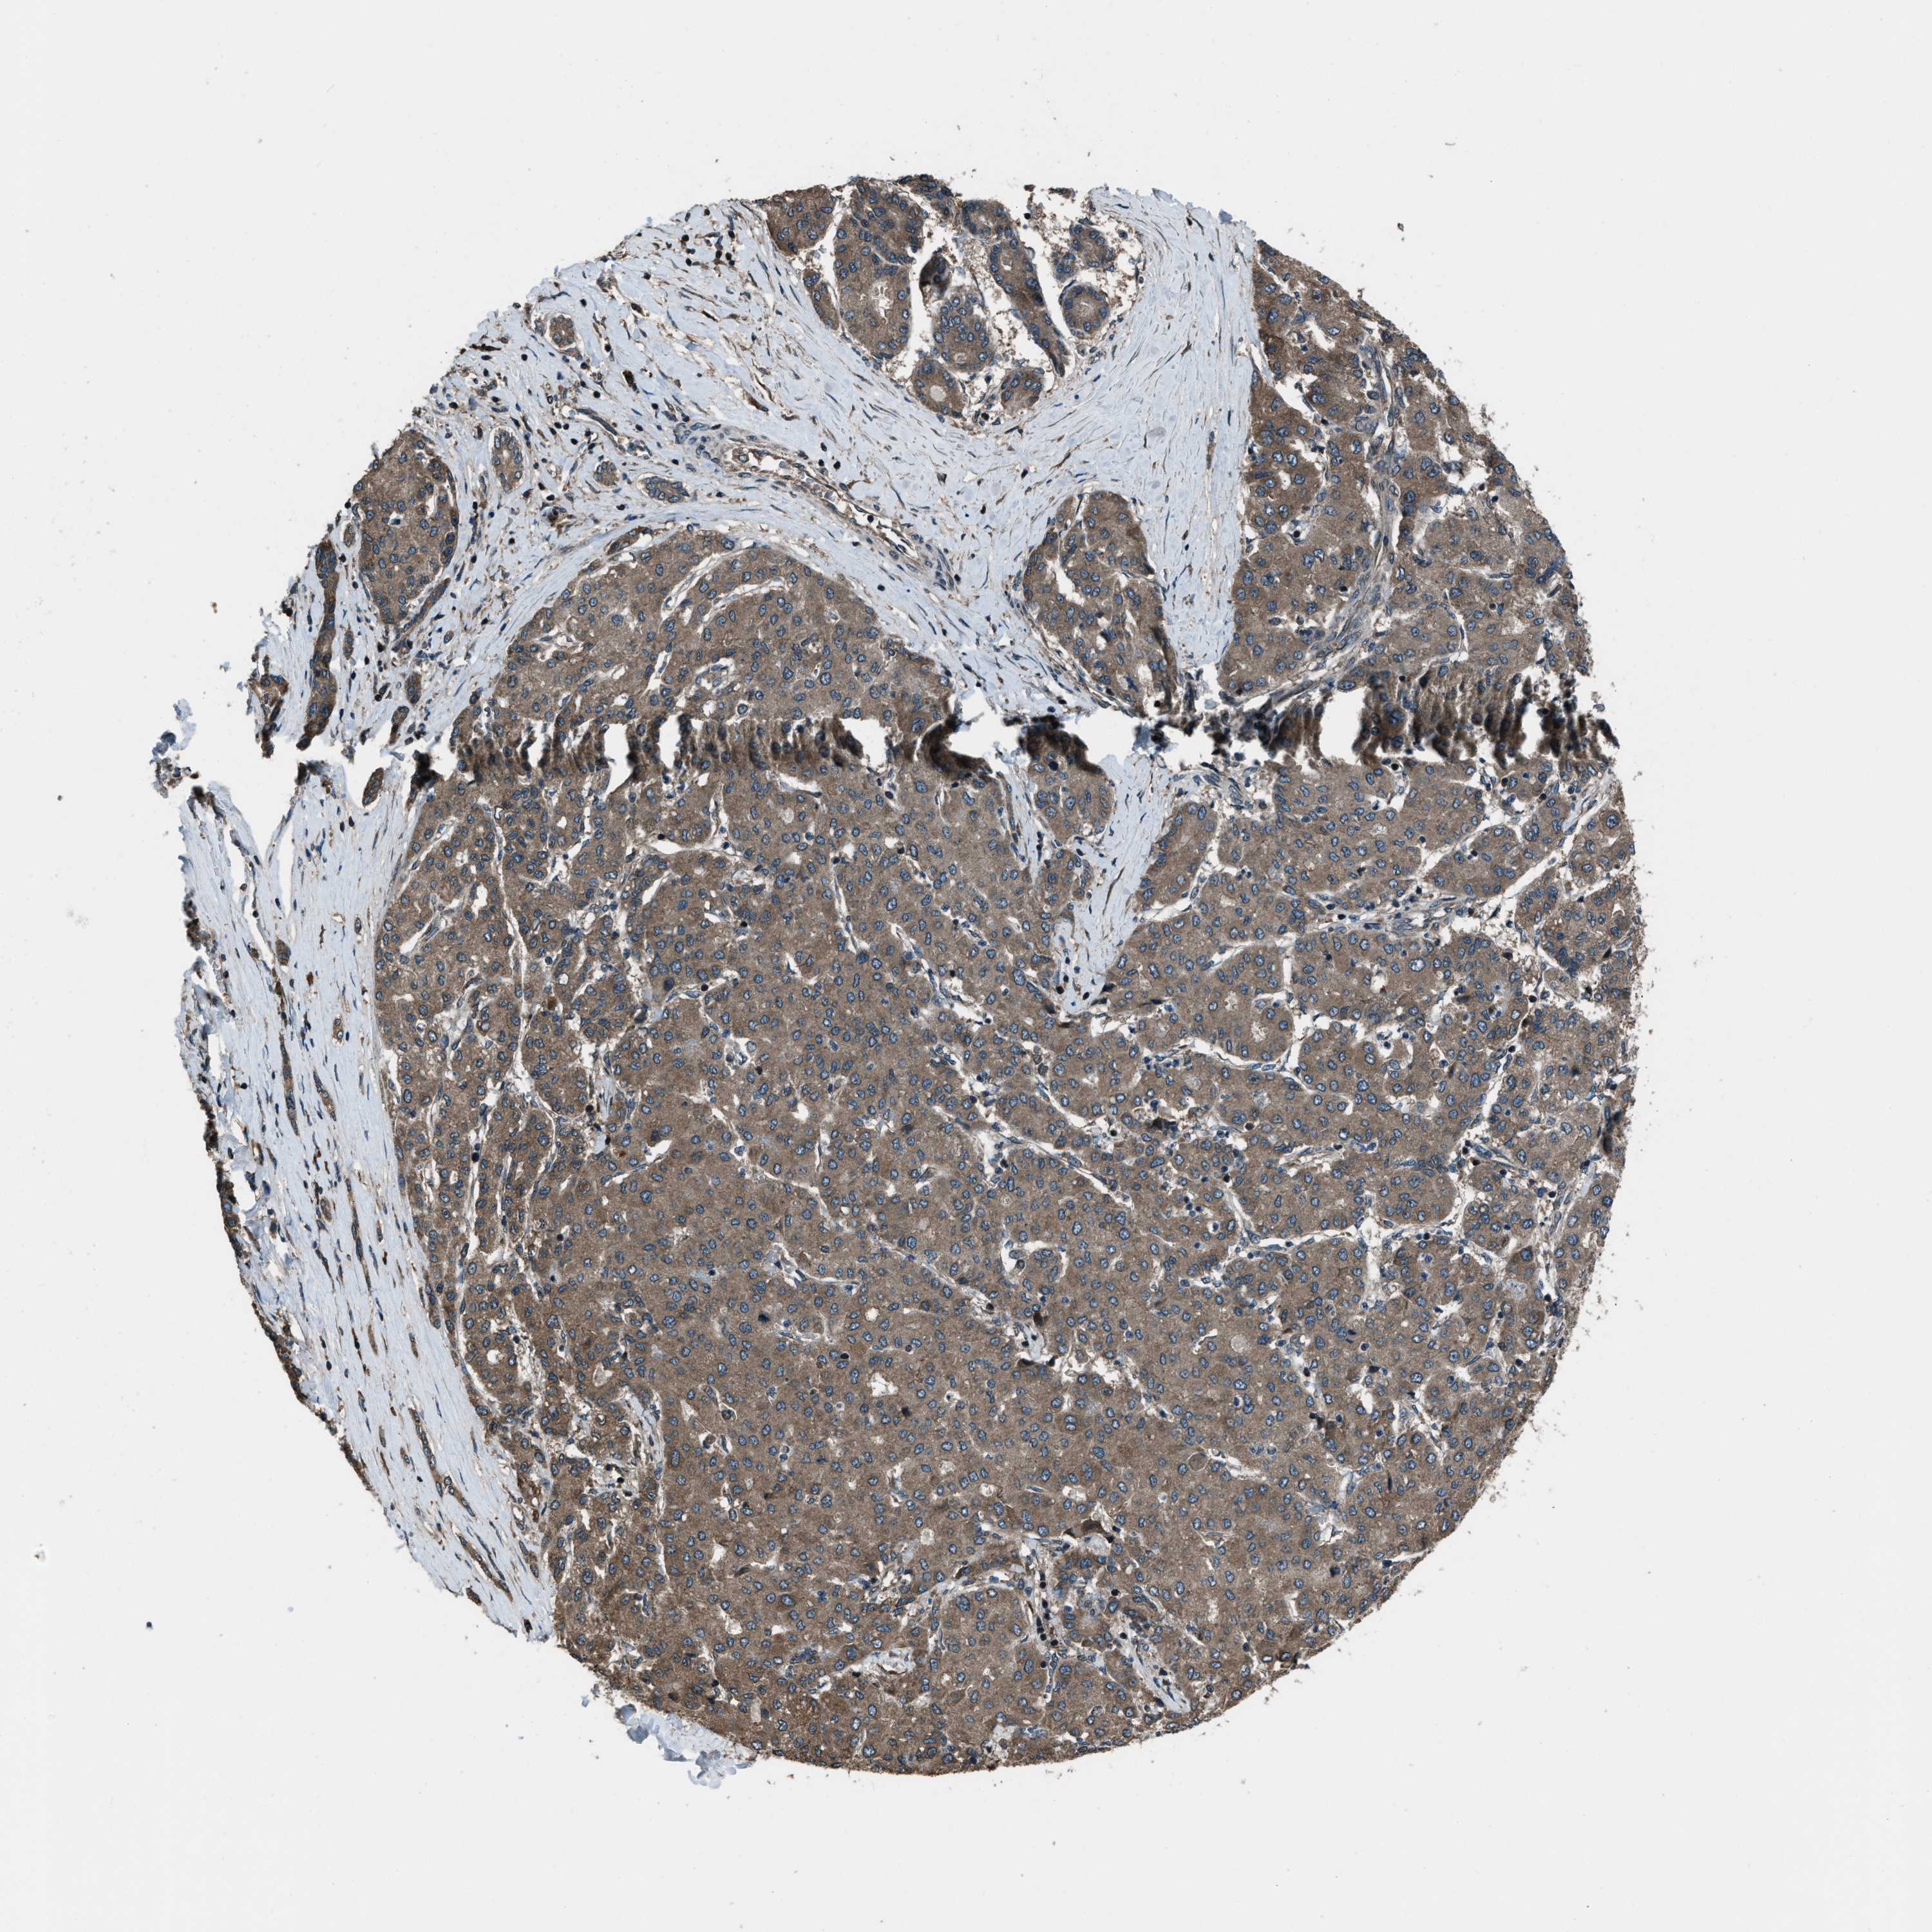

LIVER CANCER - Protein expressioni

A mouse-over function shows sample information and annotation data. Click on an image to view it in a full screen mode. Samples can be filtered based on level of antibody staining by selecting one or several of the following categories: high, medium, low and not detected. The assay and annotation is described here.

Note that samples used for immunohistochemistry by the Human Protein Atlas do not correspond to samples in the TCGA dataset.

Antibody stainingi

Antibody staining in the annotated cell types in the current human tissue is reported as not detected, low, medium, or high, based on conventional immunohistochemistry profiling in selected tissues. This score is based on the combination of the staining intensity and fraction of stained cells.

Each image is clickable and will lead to virtual microscopy that enables deeper exploration of all samples and also displays staining intensity scores, fraction scores and subcellular localization as well as patient and tissue information for each sample.

Antibody HPA019356

Antibody HPA029461

Staining

High

Medium

Low

Not detected

Intensity

Strong

Moderate

Weak

Negative

Quantity

>75%

75%-25%

<25%

None

Location

Nuclear

Cytoplasmic/membranous

Cytoplasmic/membranous,nuclear

Cholangiocarcinoma

Carcinoma, Hepatocellular, NOS